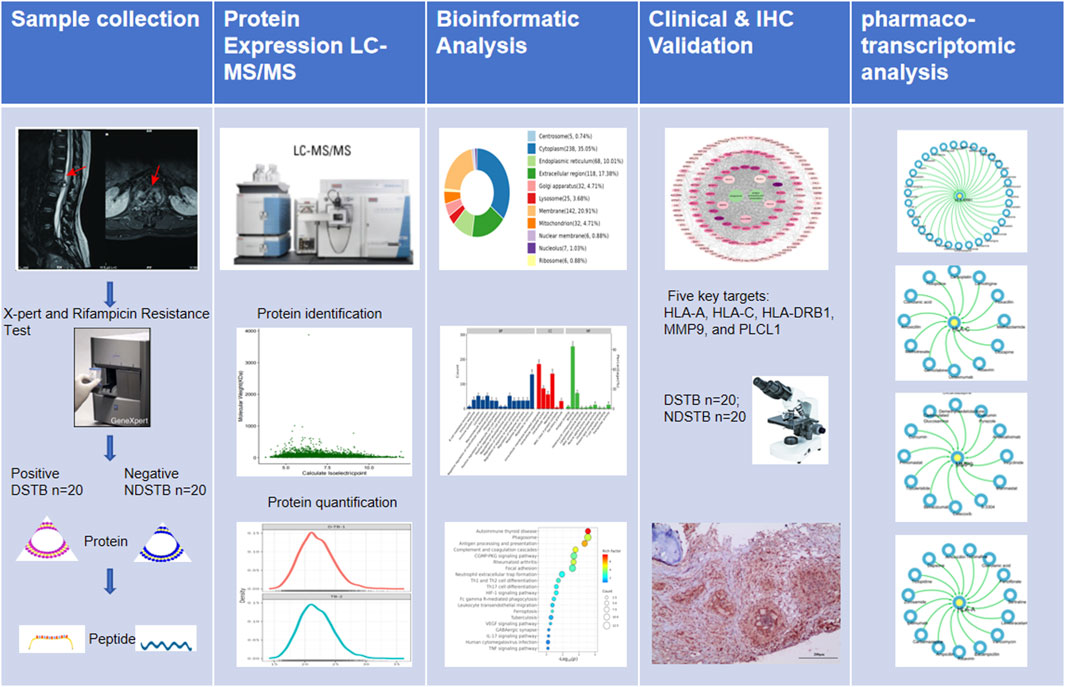

In this study, our primary focus was to identify potential targets based on proteomics and explore the mechanism of Rifampicin-resistance using pharmaco-transcriptomic analyses. The graphical abstract of our study was presented in Figure 1.

Figure 1. The graphical abstract of our study was presented.